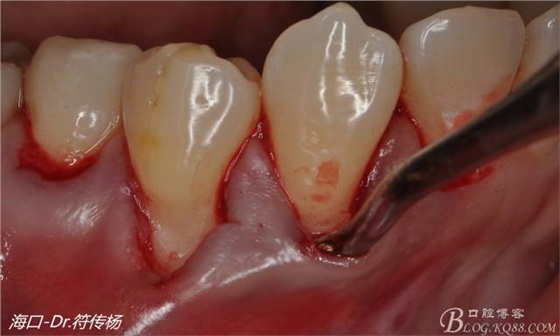

從病例圖片我們可以看到44牙頰側(cè)牙齦出現(xiàn)明顯萎縮

術(shù)前評(píng)估:退縮的齦緣在MGJ冠方 近遠(yuǎn)中牙槽嵴頂高度正常屬于Miller -Ι類牙齦退縮 所有術(shù)后可以完全覆蓋